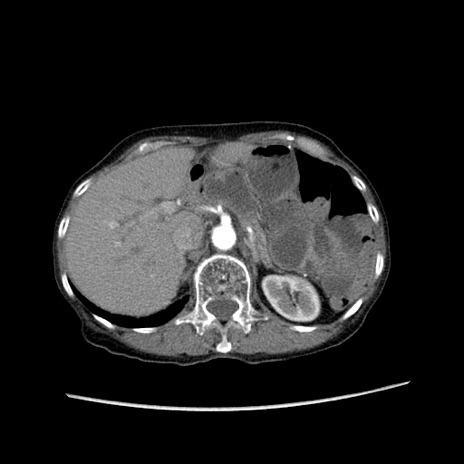

症例25(横断像)

【症例】80歳代女性

【主訴】胸のつかえ感

【現病歴】約9時間前に食後から胸のつかえた感じあり、嘔吐あり、来院。

【既往歴】胃癌(全摘)、胆摘、虫垂炎

【身体所見】心窩部に圧痛あり、反跳痛なし。

【データ】WBC 5700、CRP 0.05